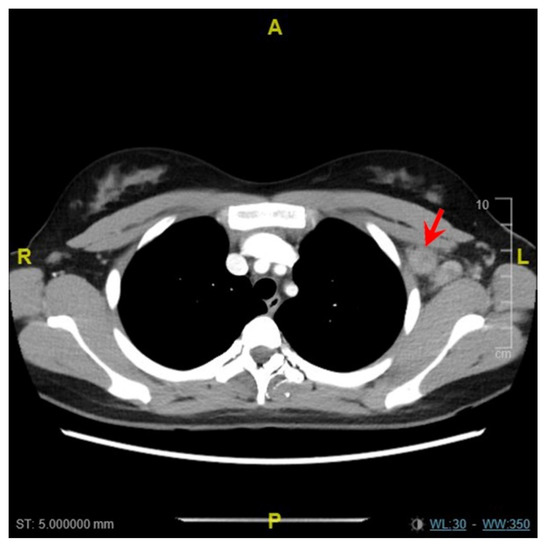

2. Case Report